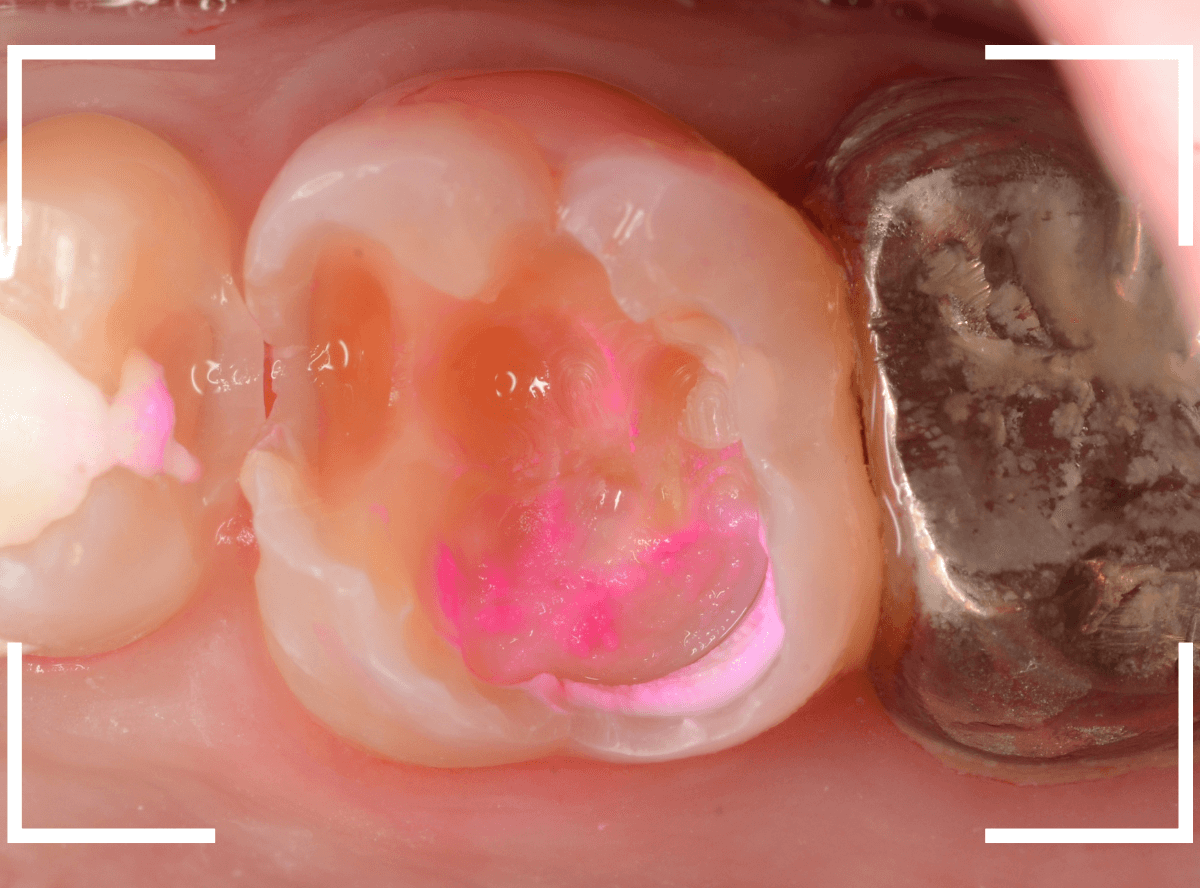

治療開始です。

まず、慎重にレジンを除去します。

レジンの中の虫歯治療で難しいのは、レジンが歯と同じ色をしているために、歯なのかレジンなのか見分けがつきにくい時がある事です。

この写真でも、レジンがまだ残っているのがわかるでしょうか?

白い〇の部分です。

レジンを全て除去しないと、その下の虫歯を取り残してしまいます。

う蝕検知液で、虫歯の部分を判別しても、レジンが残っていると、わかりづらいです。

慎重にレジンを除去すると、歯の神経が顔を出してきました(露髄)。

レジンを除去したところでもう一度染め出しをしてみます。

神経の周りも虫歯で真っ赤に染まります。

露髄した部分が広がらないように、慎重に虫歯を除去しました。

幸い、それ以上広がる事はありませんでしたので、なんとか神経が残せる可能性が高いです。

お薬とセメントをつめて、経過観察します。

痛みが出ませんように・・・。